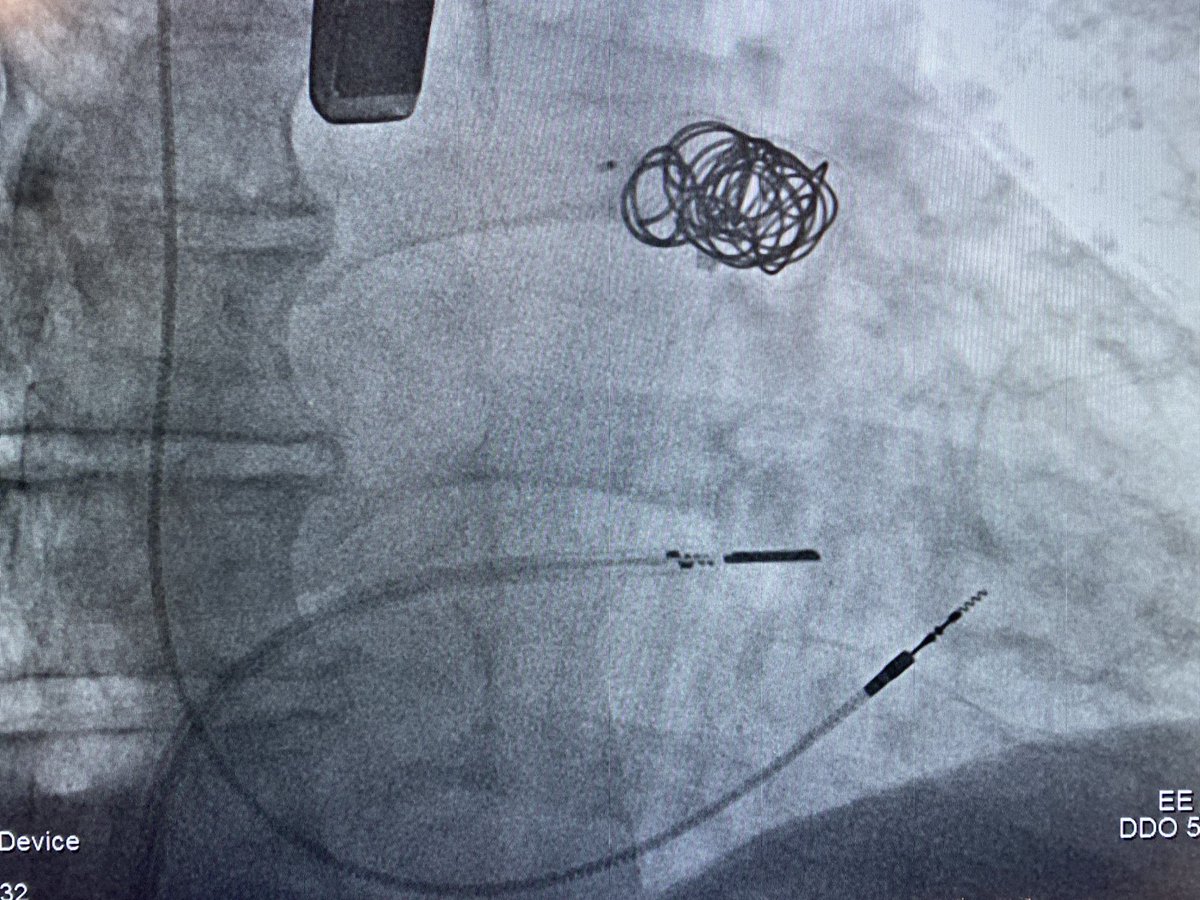

"NuVera 3D ICE in LA to image post device leak closure."

(@aalahmadmd)